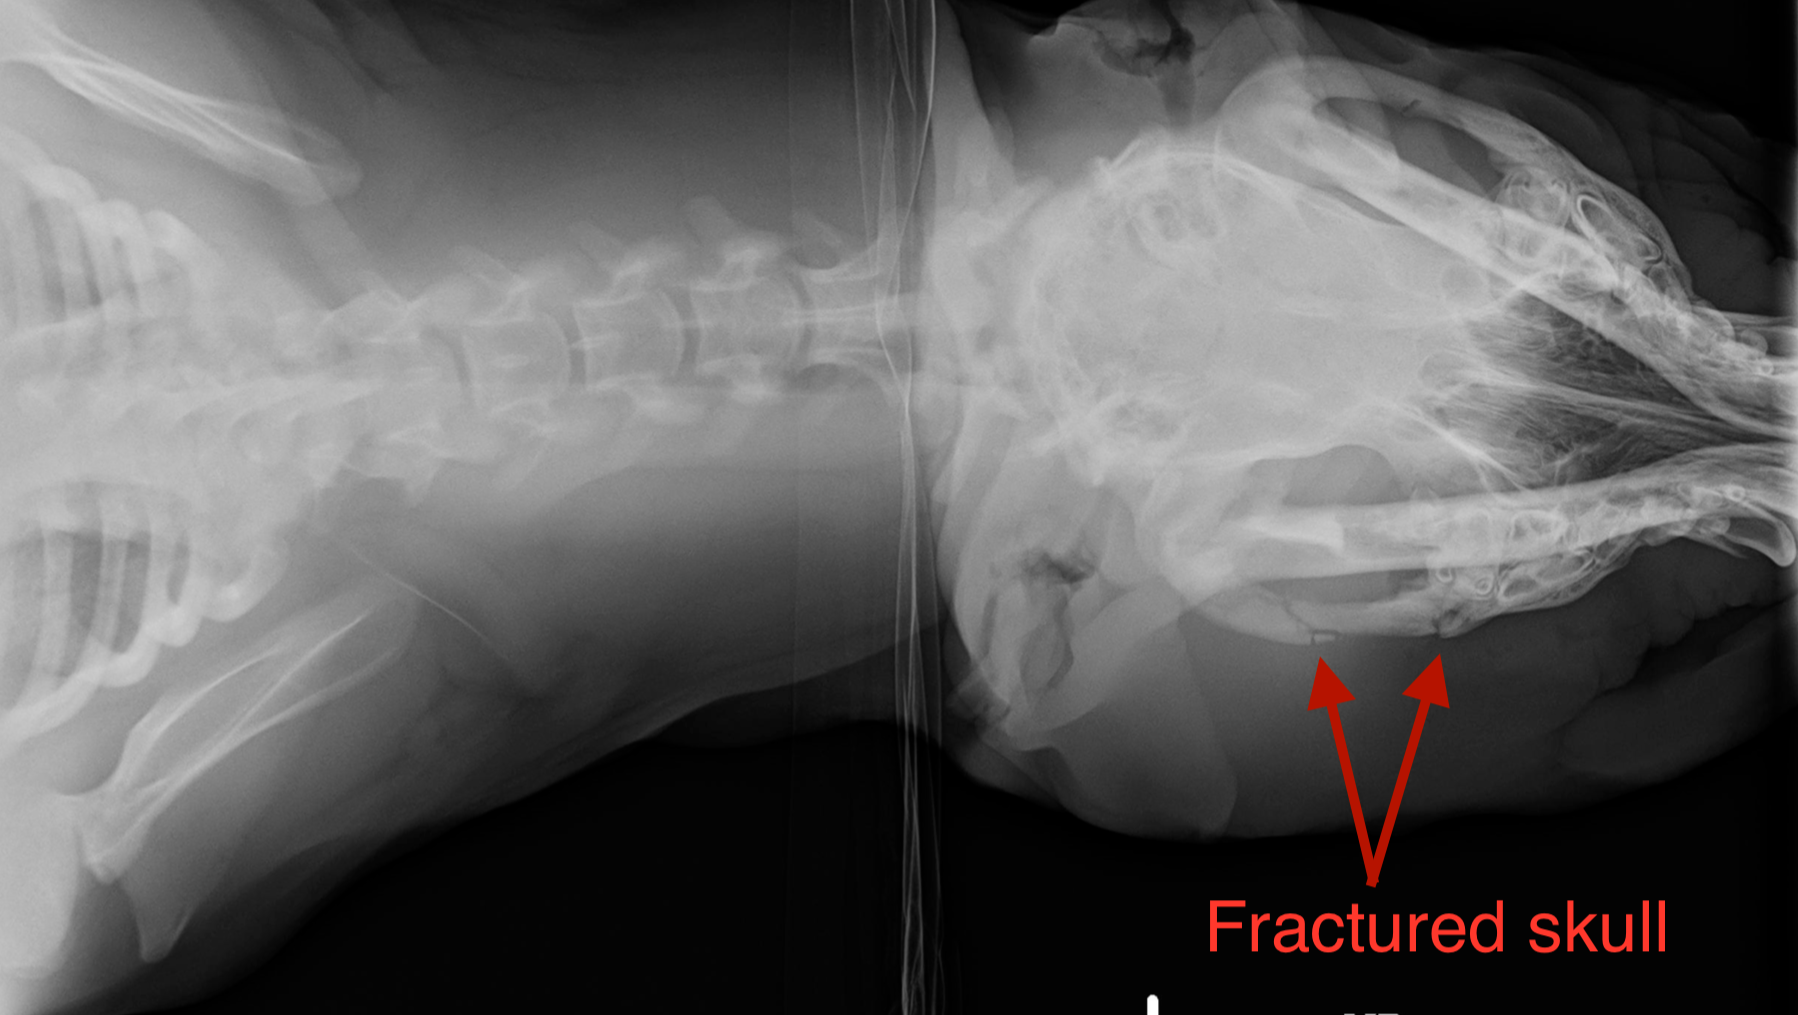

Ducky’s face and head were terribly swollen because of several skull fractures. She could not walk due to a broken hind leg, and badly deformed front limbs (partially a result of nutritional starvation). She had several broken ribs, and fractures throughout her body in different stages of healing (without treatment or medications,) and severe skin infections.